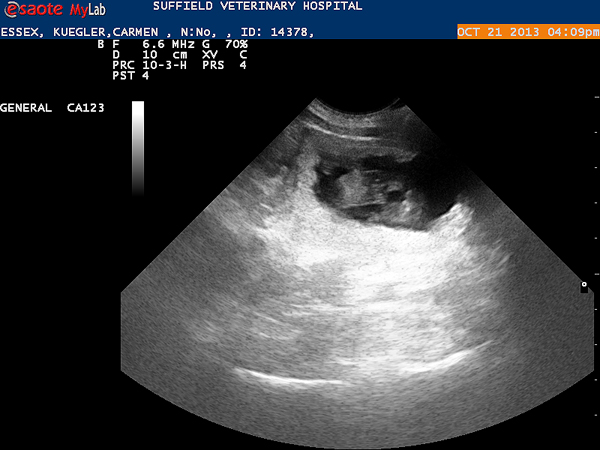

Today, on day 34th after the first mating, we did an ultrasound examination. We are very happy: Essex is pregnant. So, we look forward to her puppies in mid-November.

We could see several fetuses: